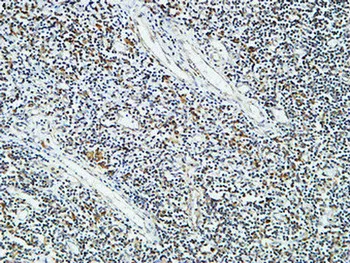

CD83 Rabbit Polyclonal Antibody

Cat: APRab08469

Size1:50μl Price1:$118

Size2:100μl Price2:$220

Size3:500μl Price3:$980

Size2:100μl Price2:$220

Size3:500μl Price3:$980